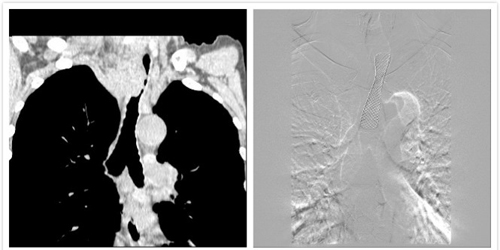

患者男,74歲。5月3日因食管癌放療后縱膈淋巴結(jié)轉(zhuǎn)移侵犯壓迫氣管致重度呼吸困難急診轉(zhuǎn)入西安高新醫(yī)院消化介入科。CT檢查示氣管重度狹窄,“命懸一線”(圖1)。急請放射科姚曉群副主任醫(yī)師、王麗峰副主任醫(yī)師會診,并積極做好術(shù)前準(zhǔn)備后,于5月4日在呼吸內(nèi)科張春芳主任醫(yī)師的全程指導(dǎo)下,在消化介入科、介入手術(shù)室及支氣管鏡室全體醫(yī)技護(hù)人員的配合下,王麗峰副主任醫(yī)師插入支氣管鏡,置入導(dǎo)絲后拔鏡,消化介入科呂良山主任醫(yī)師、曹俊飛醫(yī)師在DSA機(jī)的監(jiān)視導(dǎo)引下,氣管內(nèi)置入18x60mm鎳鈦記憶合金內(nèi)支架一枚,手術(shù)過程順利,支架位置及膨脹良好(圖2,3)。支架置入后患者呼吸困難立即消失(圖4),療效立竿見影,次日出院。

△圖1 CT示氣管重度狹窄 △圖2 正位支架位置及膨脹良好